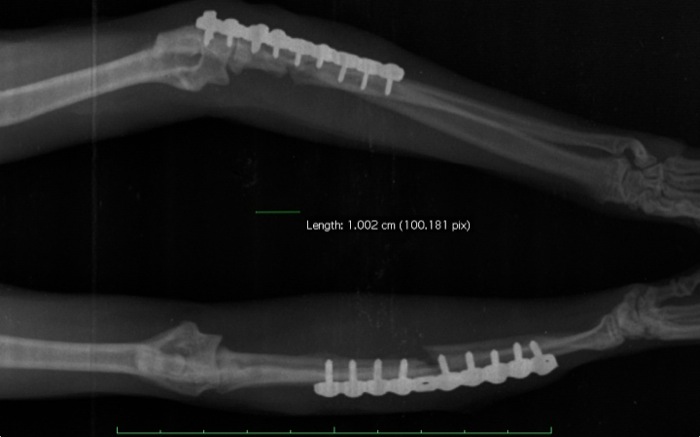

Ha durado mas de lo aconsejable la cirugía, 2h y 45 min. pero el resultado es estable con 2 corticales firmes por tornillo. La evolución a partir de aquí va a depender de un manejo estricto del entorno del paciente felino.

El resultado es satisfactorio en esta proyección y aunque el cúbito no se alinea perfectamente el apoyo con este miembro derecho es óptimo al mes.

El codo queda radiológicamente bien. Al mes utiliza ambos miembros aunque en este la recuperación aún no es completa. Es necesario esperar y dar tiempo para ver si alcanzamos la misma función que en el otro miembro con total movilidad. Aunque a nivel óseo podemos tener un buen pronóstico a medio plazo el daño articular fue muy amplio y habrá que dar tiempo para valorar la retirada en pocos meses de los implantes. A largo plazo y ante lesiones de esta envergadura siempre tenemos el riesgo de la aparición de artrosis